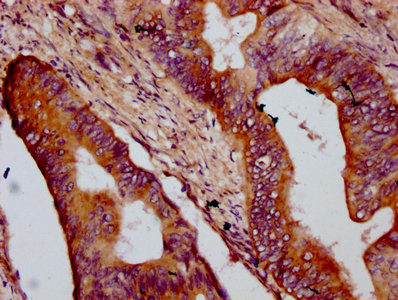

IHC image of CSB-PA752530LA01HU diluted at 1:400 and staining in paraffin-embedded human colon cancer performed on a Leica BondTM system. After dewaxing and hydration, antigen retrieval was mediated by high pressure in a citrate buffer (pH 6.0). Section was blocked with 10% normal goat serum 30min at RT. Then primary antibody (1% BSA) was incubated at 4°C overnight. The primary is detected by a biotinylated secondary antibody and visualized using an HRP conjugated SP system.